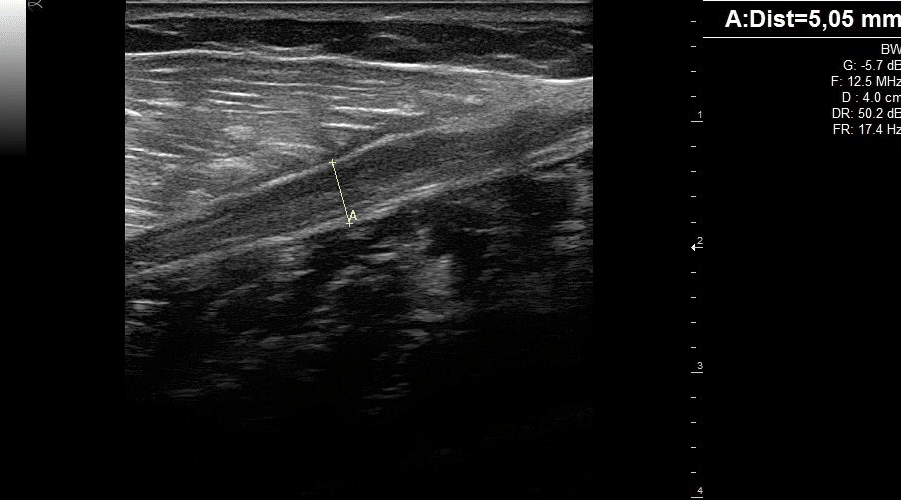

L’échographie en médecine du sport apporte de nombreux avantages à votre pratique quotidienne. L’échographie permet l’évaluation en en temps réel de nombreuses pathologies : lésions musculaires, tendinopathies, pathologies ligamentaires, inflammation des tissus mous, microfractures… L’examen des clichés permet ensuite une prise en charge approfondie du patient un suivi poussé de la guérison.

L’aide à la ponction avec le guide sous échographie de l’aiguille améliore la qualité des soins. Par l’aide à la ponction sous échographie avec le guide aiguille améliore la qualité des soins. Vous profitez d’une aide à la ponction grâce aux guides aiguilles qui améliorent la qualité des soins.